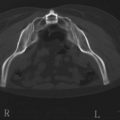

All areas of infiltration should be approached from at least two directions. This provides more structural integrity as the fat is laid down in a cross-hatched fashion. In this specific situation, access incisions in the buttock and thigh were chosen to allow placement perpendicular and longitudinal to the buttocks crease (Figs 47.1–47.4).